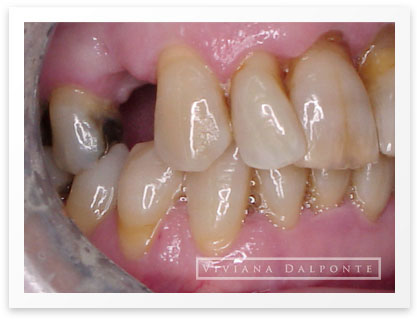

CASO 6: Restauración con prótesis fija en ambos maxilares